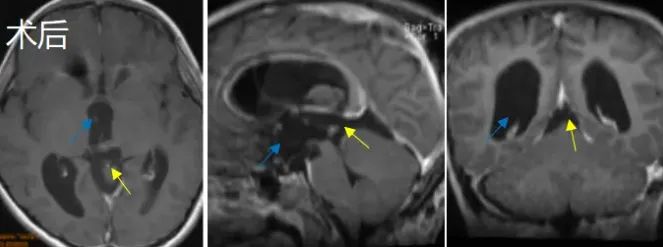

术后过程

术后第一天晃晃意识清醒,在ICU监护两天后情况稳定,未出现明显并发症,无小脑肿胀表现,顺利出院。患儿术前各种症状逐渐消失,机体功能恢复正常,近期复查未见肿瘤复发。

案例来源:Bertalanffy, H. Avoidance of postoperative acute cerebellar swelling after pineal tumor surgery. Acta Neurochir 158, 59–62 (2016).